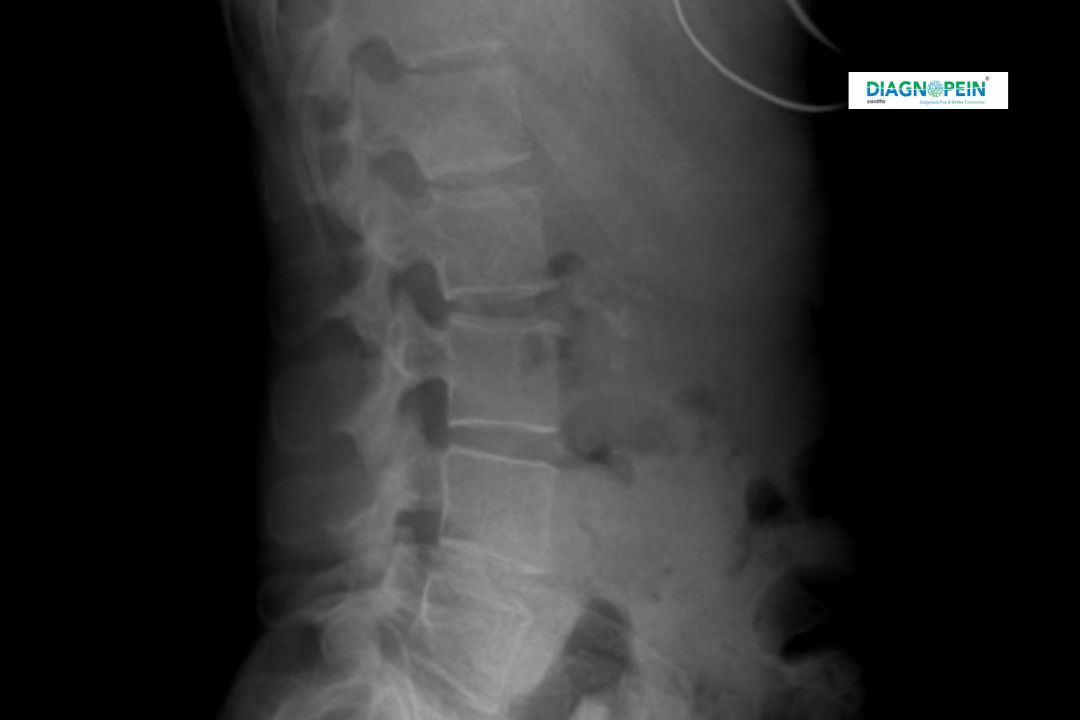

An X-Ray Dorsal Spine AP/Lateral (Anteroposterior and Lateral) View is a specialized diagnostic imaging test used to capture detailed images of the thoracic (mid-back) spine. The two projections—AP and lateral—help visualize vertebral alignment, bone density, and any signs of trauma or disease.

• Two images are taken – one from the front (AP view) and one from the side (lateral view).

1. Spine alignment and vertebral body height

2. Detection of fractures, deformities, or infection

3. Evaluation of disc space narrowing or osteophyte formation

4. Postoperative and trauma follow-up

5. Assessment of kyphosis or other structural changes

These detailed parameters help clinicians diagnose conditions like compression fractures, scoliosis, spondylitis, and other thoracic spine pathologies.